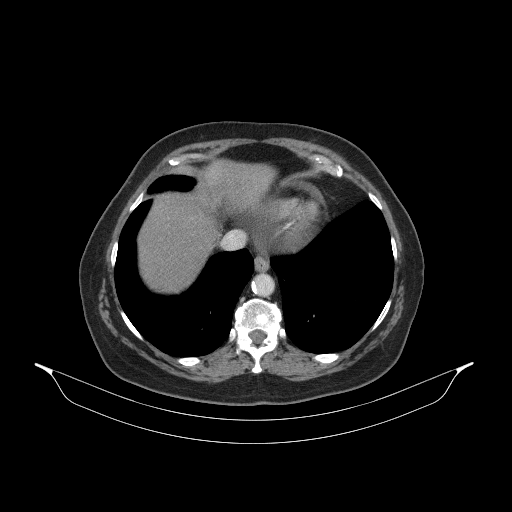

Generated VENOUS CT scan (A→B translation)

Full window (WL 1023.5, WW 4095 β†’ Low βˆ’1024, High +3071)

Lung window (WL -600, WW 1500 β†’ Low βˆ’1350, High +150)

Mediastinum window (WL 40, WW 400 β†’ Low βˆ’160, High +240)